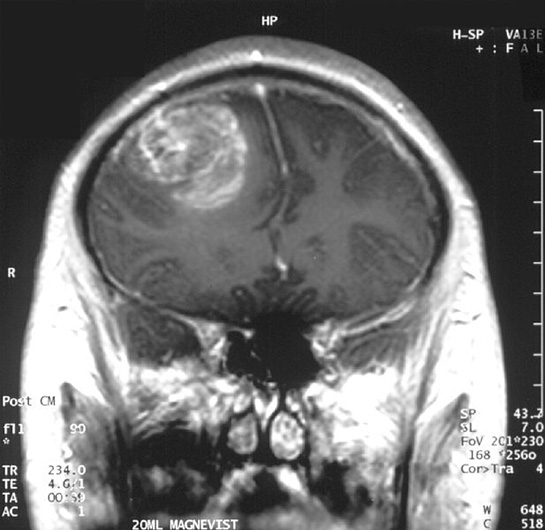

Tümör Sınıflaması Nedir?Tümör sınıflaması, kanserin tanısını koymak, tedavi planlamasını yapmak ve prognozu değerlendirmek amacıyla tümörlerin belirli kriterlere göre gruplandırılmasıdır. Bu sınıflama, tümörlerin histolojik özelliklerine, büyüme şekline, evresine ve metastaz durumuna göre yapılmaktadır. Tümörlerin sınıflandırılması, klinik pratiğin önemli bir parçasıdır ve onkologlar tarafından hastaların tedavi süreçlerinde rehberlik etmek amacıyla kullanılır. Tümör Sınıflama SistemleriTümör sınıflaması için birçok sistem geliştirilmiştir ve bunlar genellikle şu başlıklar altında toplanır:

Histopatolojik Sınıflama Histopatolojik sınıflama, tümörlerin mikroskop altında incelemesiyle yapılan bir değerlendirmedir. Bu sınıflama, tümörlerin kaynaklandığı doku tipine göre yapılır ve genellikle şu başlıkları içerir:

Histopatolojik sınıflama, tümörlerin malignite potansiyelini belirlemede kritik bir rol oynamaktadır. Evrelendirme (Staging) Evrelendirme, tümörün vücutta ne kadar yayıldığını belirlemek için kullanılan bir sistemdir. En yaygın evrelendirme sistemi, TNM sistemidir ve üç ana unsurdan oluşur: